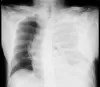

Small-Bore vs. Large-Bore Chest Tubes: Does Size Really Matter for Hemothorax and Pleural Effusions?

For decades, the belief that “bigger is better” has driven the choice of chest tube size for managing hemothorax and pleural effusions. Yet a growing…